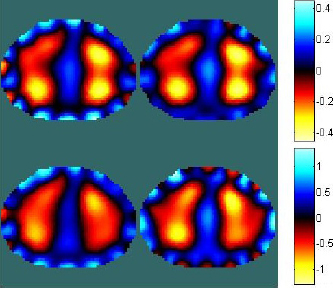

Images were reconstructed with the traditional approach using the measured voltages and with the above described methods where obtained voltages are modified based on simulations on homogeneous FEM models.

Reconstructed conductivity of frame 16. Left: Reconstruction with traditional approach. Right: Approach using modified boundary voltage based on precise FEM mesh. Red colour indicates decreasing conductivity.

Results indicate that for every considered frame, the amount of boundary artefacts is reduced when the precise FEM mesh is used to calculate the modification of boundary voltages used for image reconstruction according to Eq. 4 and Eq. 1. Figure 3 shows the reconstructed conductivities of frame 16.

If the simplified mesh is used to modify the boundary voltages the amount of artefacts is reduced if thorax deformations are small, at higher deformations more boundary artefacts arise (Figure 4). Please note that the colouring is different for every frame to ensure that details in reconstructed conductivity can be identified more easily.

Upper row: Reconstructed conductivities at frame 8. Lower row: Reconstructed conductivities at frame 20. Left column: Reconstruction with traditional approach. Right column: Reconstruction with modified voltages based on stretched FEM model (simplified mesh).